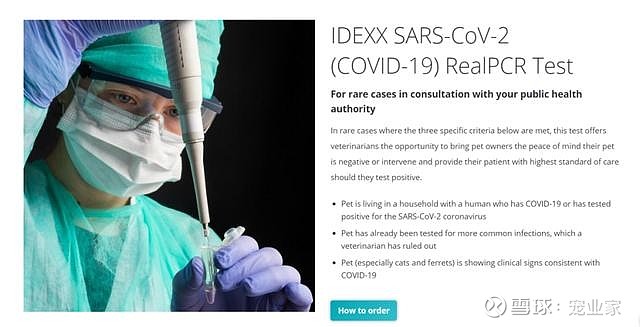

美国发现宠物阳性案例爱德士推广宠物用新冠检测试剂盒

图片尺寸640x327